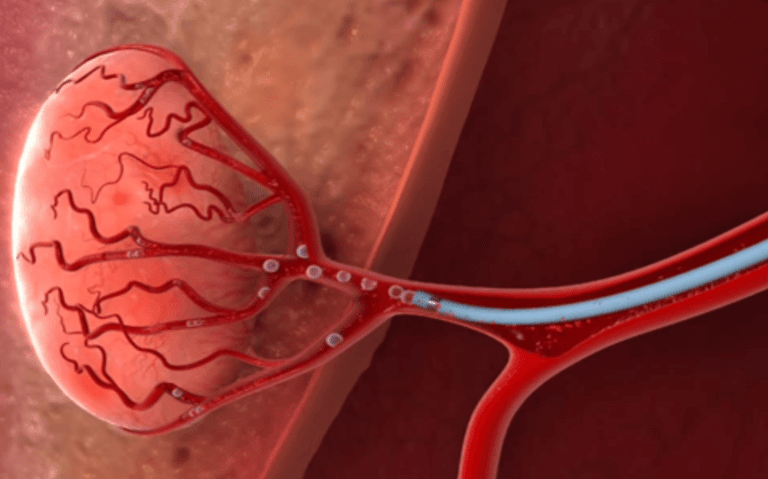

Embolização de mioma uterino

Embolização prostática